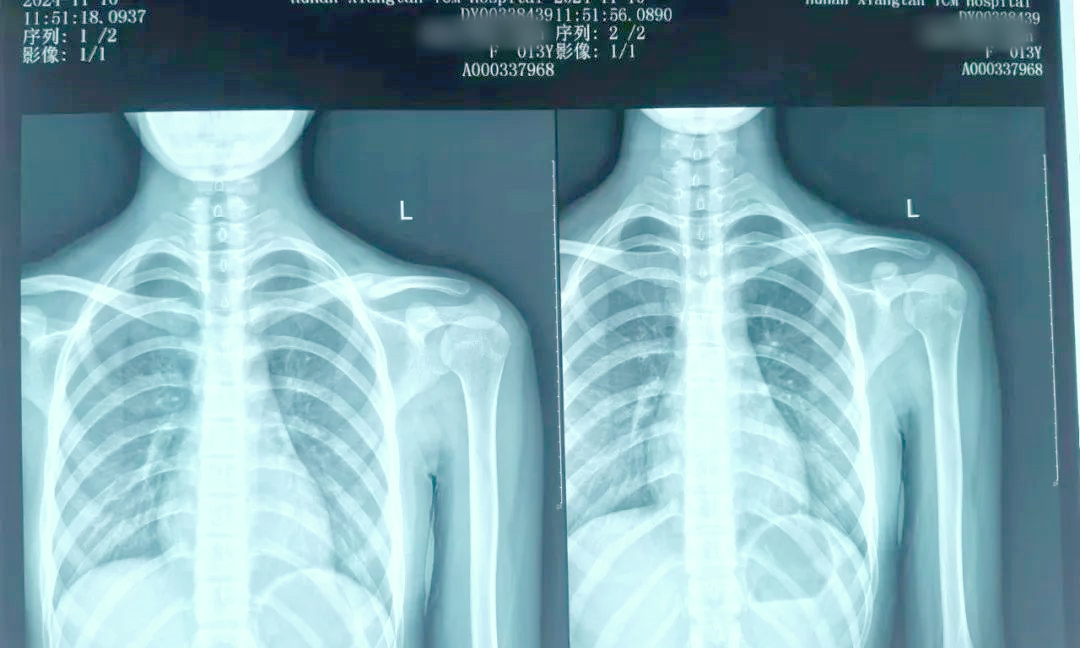

9岁男孩锁骨骨折是保守治疗还是手术治疗?

⚡️宝宝摔跤锁骨疑骨折,带娃急诊拍片🏥